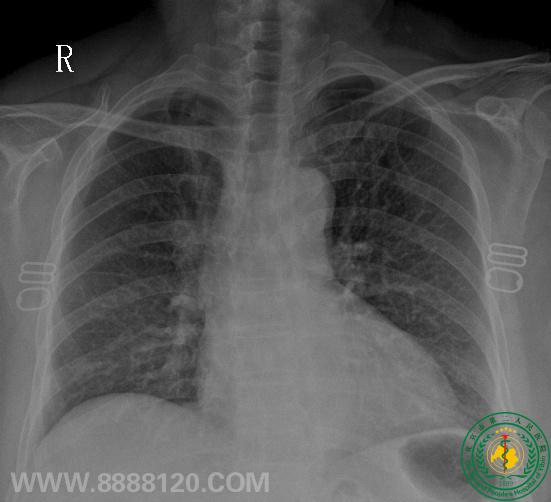

病例2:MRI发现脑转移瘤                       X线胸片右上肺少许炎变                           PET/CT发现右肺门中央型Ca